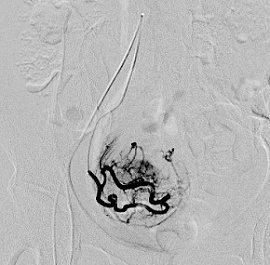

子宮筋腫に対する子宮動脈塞栓術(UAE)の実際

子宮動脈塞栓術(UAE)とは、子宮筋腫に栄養を与えている子宮動脈の血流を止めること

によって、筋腫を縮小させ、筋腫によって生じる過多月経などの症状を改善する治療法

です。足のつけ根に局所麻酔を行い、足のつけ根の動脈にカテーテルを入れ筋腫の近く

まで進めます。カテーテルから塞栓物質を注入し、血管を塞ぎ血流を止めます。塞栓が

完了したらカテーテルを抜き、傷口を押さえて止血します。

血管描出(塞栓前) 血管描出(塞栓後)

塞栓前MRI画像 塞栓後MRI画像